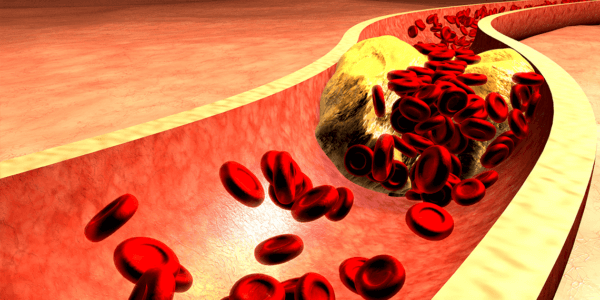

En France comme dans tous les pays industrialisés, les problèmes cardiovasculaires représentent la première cause de mortalité.

S’il y a certains facteurs de risques face auxquels nous sommes impuissants (l’âge, le sexe ou l’hérédité), il y en a d’autres, heureusement, sur lesquels nous pouvons agir. Hypertension artérielle, excès de cholestérol, excès de sucre dans le sang (hyperglycémie) peuvent être maîtrisés en modifiant nos habitudes de vie (alimentation plus saine, exercices physiques…) et en ayant recours aux solutions d’origine naturelle appropriées.